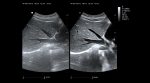

Imágenes con filtro espacial adaptativo – zonClear

ViV 20 está configurado con un algoritmo avanzado de filtro espacial adaptativo y se combina con una técnica de filtrado temporal con compensación de movimiento. Reduce eficazmente el ruido de speckle y mejora significativamente la visualización de los límites tisulares y la visualización del eco tisular mediante la detección de la ubicación de los límites anatómicos.

Imágenes clínicas extraordinarias